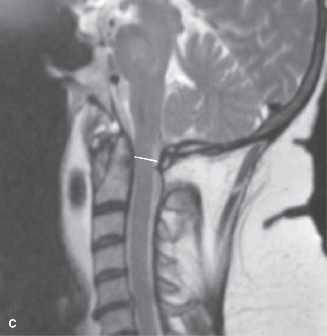

To evaluate the neural elements and the soft tissue structures, a comprehensive MRI of the lumbar spine without contrast was obtained. The T2-weighted sagittal and axial sequences confirmed the Grade 2 anterolisthesis and demonstrated severe bilateral foraminal stenosis at L5-S1. The exiting L5 nerve roots were severely compressed between the hypertrophied, fibrocartilaginous pseudarthrosis tissue of the pars defect dorsally, and the bulging, degenerated L5-S1 disc and superior endplate of S1 ventrally. Furthermore, the MRI revealed Modic Type II changes (fatty replacement of the subchondral bone marrow) in the adjacent vertebral endplates, confirming chronic biomechanical stress and discogenic degeneration. The central canal remained relatively patent, which is characteristic of isthmic spondylolisthesis, as the posterior neural arch is left behind during the anterior translation of the vertebral body.

Five years later, the patient, now a 20-year-old collegiate athlete, presented back to our clinic with a drastically altered clinical picture. He was now experiencing severe, unrelenting, and constant pain in his lower back that severely limited his mobility. Crucially, the pain character had evolved; he now reported sharp, shooting, electric-like pain radiating from his lower back, deep into his left posterior buttock, and extending down the lateral aspect of his left thigh and calf. This transition from purely axial mechanical pain to a profound radicular symptom complex indicates that the underlying pathology had progressed from a localized bony defect to a structural instability causing direct neural compression. The progressive anterior slip of L5 on S1 had led to dynamic foraminal stenosis, trapping the exiting L5 nerve root against the fibrocartilaginous mass of the pars nonunion and the superior endplate of S1.

When the patient returned five years later with a Meyerding Grade 2 isthmic spondylolisthesis, severe L5 radiculopathy, and MRI evidence of L5-S1 disc degeneration, the treatment paradigm shifted entirely to surgical intervention. The Meyerding classification grades the severity of the slip based on the percentage of anterior translation of the superior vertebral body over the inferior one: Grade 1 (0-25%), Grade 2 (26-50%), Grade 3 (51-75%), Grade 4 (76-100%), and Spondyloptosis (>100%). For a symptomatic Grade 2 slip that has failed conservative management (or in this case, progressed due to non-compliance), surgical stabilization is definitively indicated. The primary goals of surgery are twofold: first, to decompress the compromised neural elements (the L5 nerve roots), and second, to achieve a solid bony arthrodesis to halt further progression and eliminate mechanical back pain.